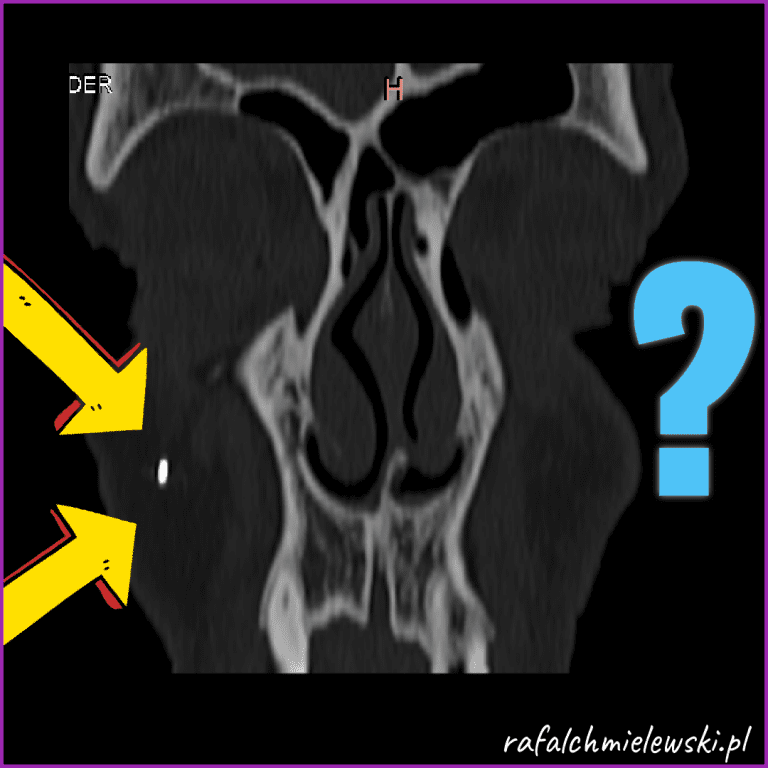

Jakie jest ryzyko zabiegu endoskopowego usunięcia torbieli zatoki szczękowej? Godziny 13 listopada 202513 listopada 2025

Jakie jest ryzyko bólów głowy w obecności małej torbieli zatoki szczękowej? Godziny 13 listopada 202513 listopada 2025